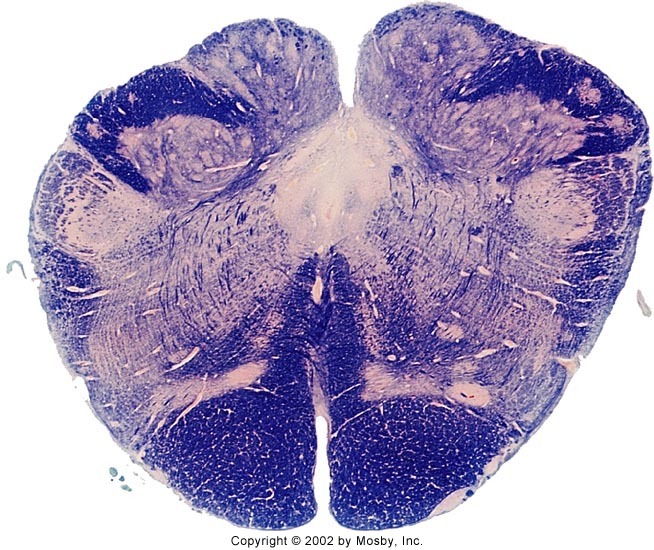

What section of the brainstem does this image come from?

caudal medulla